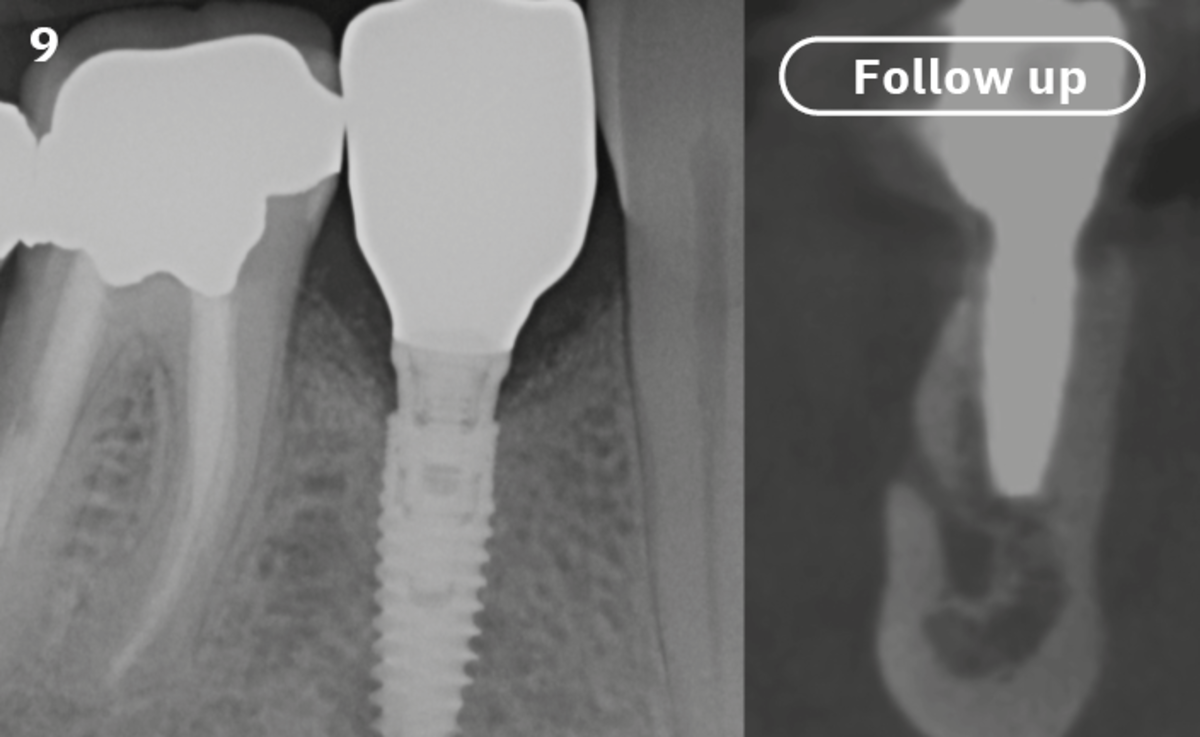

Extraction socket management with REGENFAST®

Ridge reconstruction before implant placement

The patient (45 years old, female, non-smoker, no previous pathologies) is referred for extraction of tooth 45 and immediate implant placement. The site showed an increased probing depth and a marked bone loss.